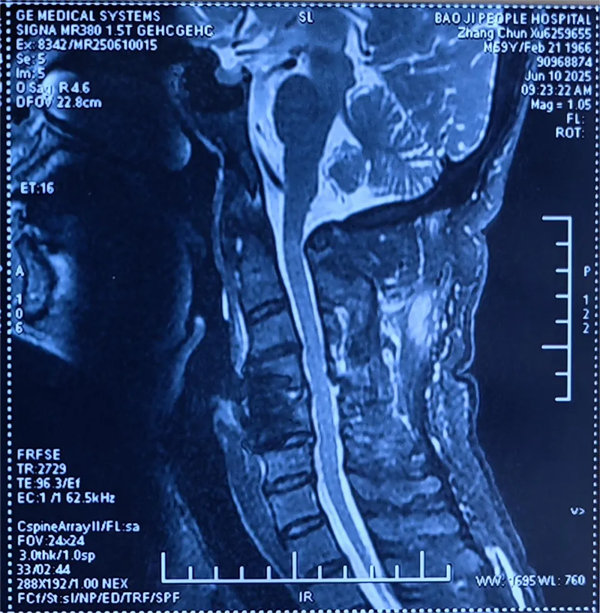

術(shù)后

患者受傷后曾在外院接受保守治療,但肢體麻木癥狀持續(xù)存在。轉(zhuǎn)入我院時,頸椎CT及MRI顯示:頸4/5椎骨折脫位,脊髓受壓明顯,若不手術(shù)治療,可能面臨永久性神經(jīng)功能障礙。我院骨四科團(tuán)隊(duì),制定了前路ACDF手術(shù)方案:通過頸前側(cè)入路,切開復(fù)位、切除椎間盤,解除脊髓壓迫,同時植入融合器、鈦板固定,重建頸椎正常序列及穩(wěn)定性。術(shù)后患者麻木感消失,復(fù)查顯示頸椎序列恢復(fù)良好,目前已康復(fù)出院。